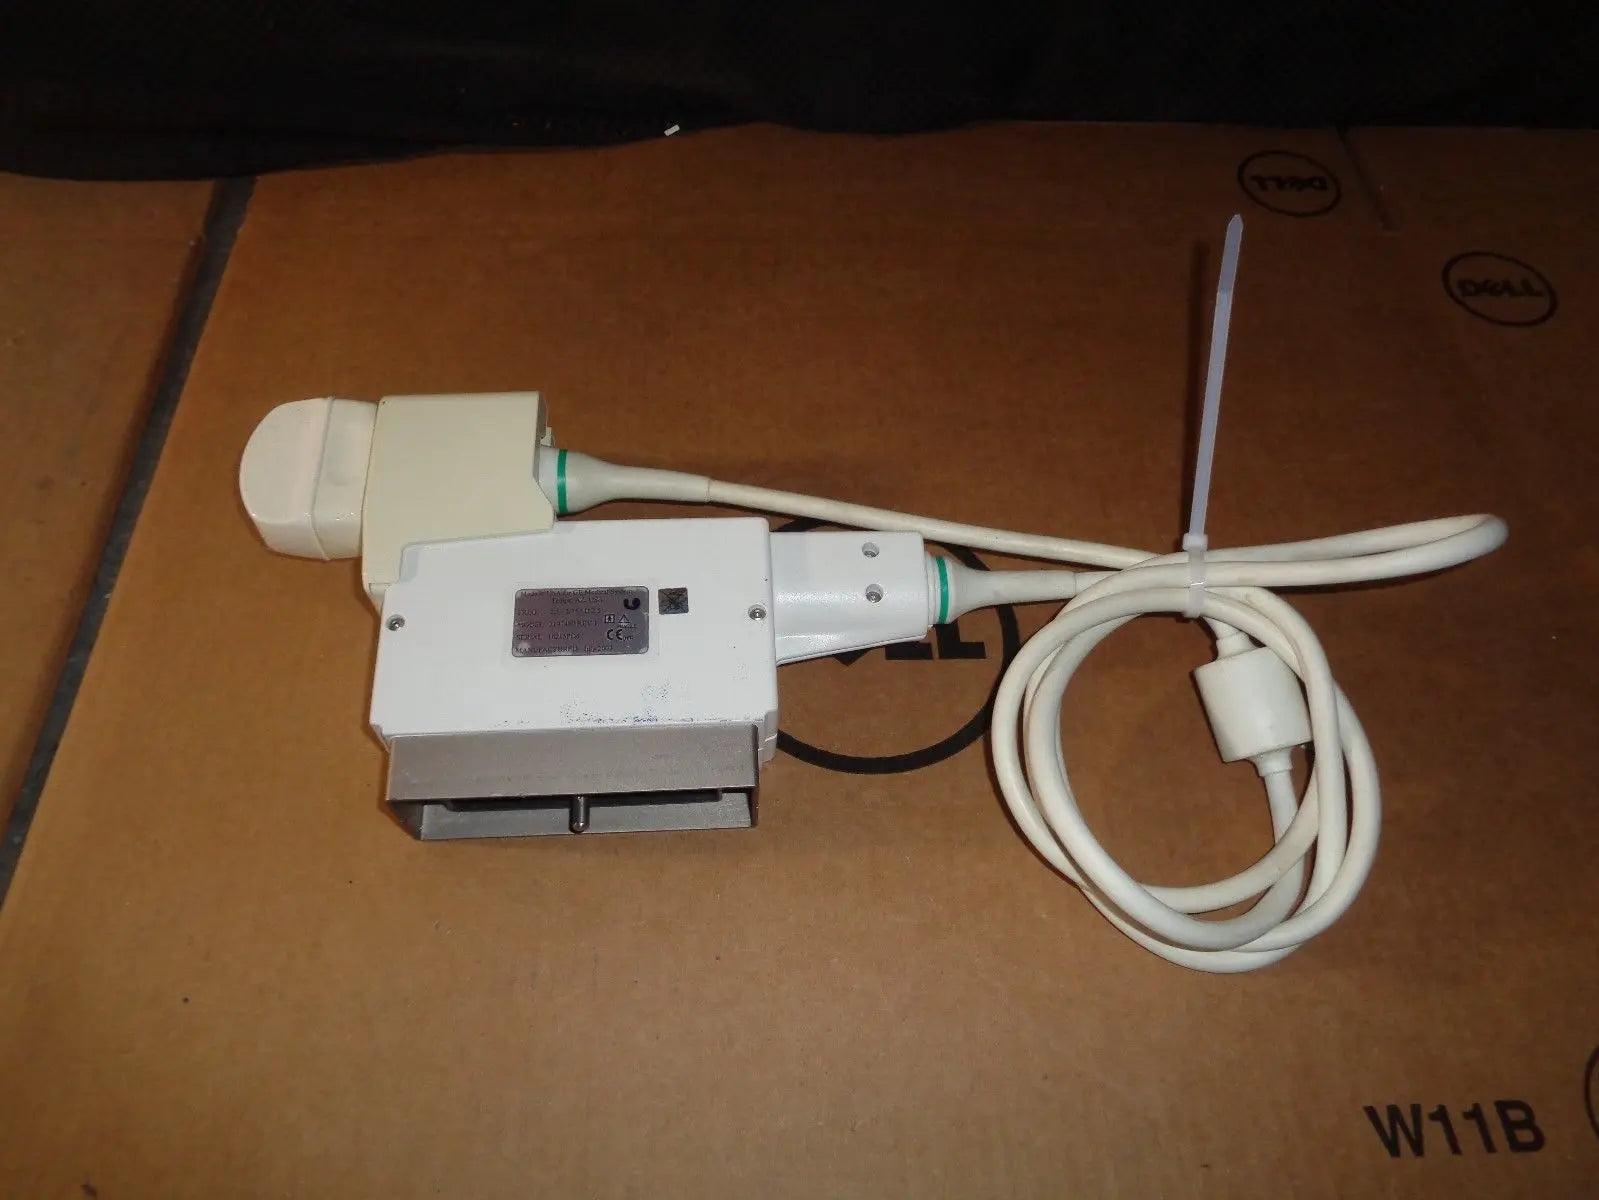

DIAGNOSTIC ULTRASOUND MACHINES FOR SALE

GE 348c Ultrasound convex ultrasound transducer

Sale price$ 1,439.90

DIAGNOSTIC ULTRASOUND MACHINES FOR SALE

GE 348C 2197480 ULTRASOUND TRANSDUCER PROBE

Sale price$ 3,599.78